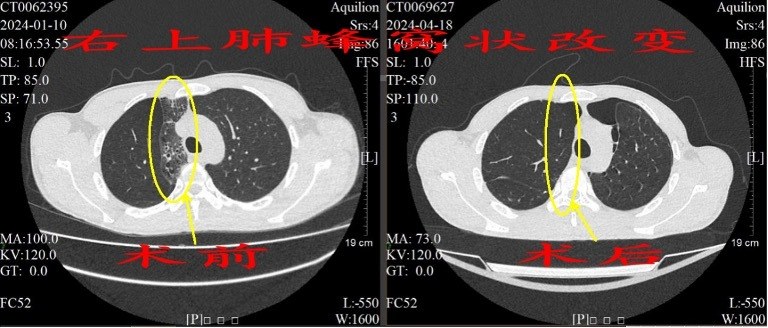

术前双侧“蜂窝”肺 术后终于消除

微创手术方案分两期实施,在2024年1月,张才铭为陈先生切除了右上 “蜂窝”肺;同年3月,二期手术切除了左下 “蜂窝”肺及左上舌段“蜂窝”肺,两次手术病理标本均证实为先天性肺囊性腺瘤样畸形(CCAM)。术后,继续加强抗感染,直至陈先生恢复良好,咳嗽咳痰症状消失,近日顺利出院。